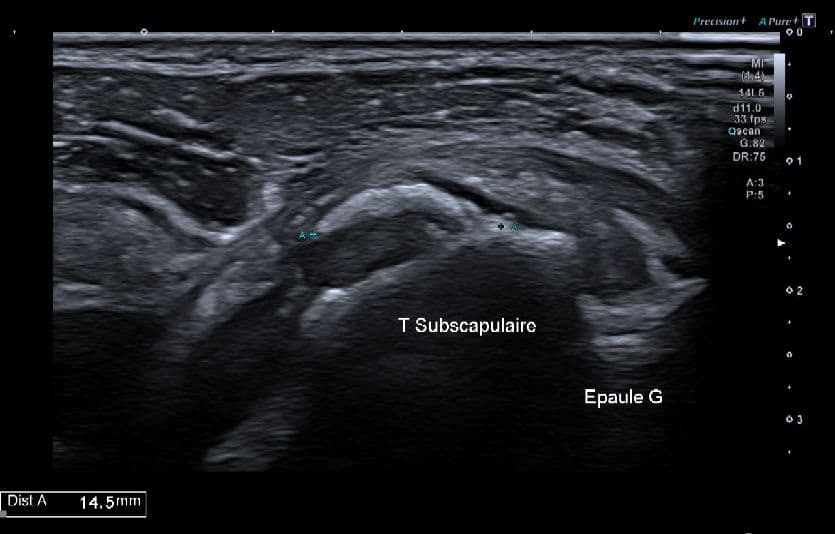

Résorption calcique aigue du tendon sous-scapulaire

Présentation clinique

Douleur insomniante subaiguë non traumatique de l'épaule gauche

Échographie

Calcification non atténuante fragmentée de 15 mm, franchement active en Doppler, et sensible à la pression sous la sonde.